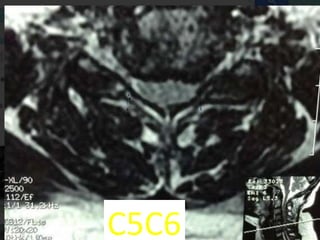

c5c6

48 year old man with right fifth finger pain and numbess